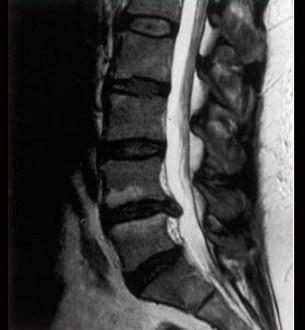

问题 如图,硬膜外间隙哪项不对 ( )

选项 A、在下颈部宽约1.5~2mm B、上自枕骨大孔,下至骶2 C、在腰处最宽约5~6mm D、在中胸部宽约3~5mm E、是一充满脂肪.血管和淋巴管的潜在间隙

答案 B